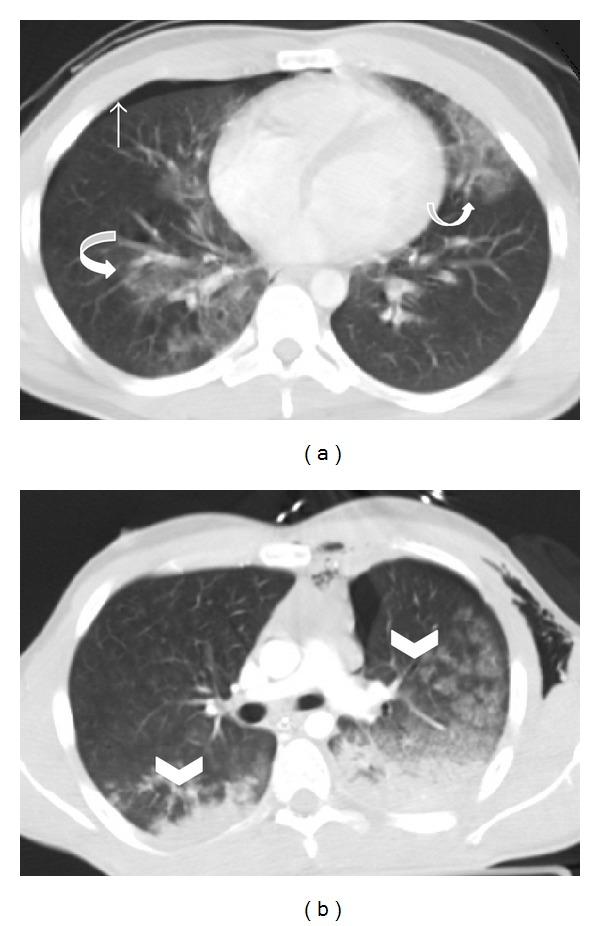

Imaging plays an essential part of chest trauma care. By definition, the employed imaging technique in the emergency setting should reach the correct diagnosis as fast as possible. In severe chest blunt trauma, multidetector computer tomography (MDCT) has become part of the initial workup, mainly due to its high sensitivity and diagnostic accuracy of the technique for the detection and characterization of thoracic injuries and also due to its wide availability in tertiary care centers. The aim of this paper is to review and illustrate a spectrum of characteristic MDCT findings of blunt traumatic injuries of the chest including the lungs, mediastinum, pleural space, and chest wall.

影像学在胸部创伤治疗中起着至关重要的作用。根据定义,在急诊环境中所采用的影像学技术应尽快得出正确诊断。在严重胸部钝性创伤中,多排螺旋计算机断层扫描(MDCT)已成为初始检查的一部分,这主要归因于该技术在检测和鉴别胸部损伤方面具有高敏感性和诊断准确性,还归因于其在三级医疗中心广泛可用。本文旨在回顾并阐述胸部钝性创伤包括肺、纵隔、胸膜腔和胸壁的一系列MDCT特征性表现。